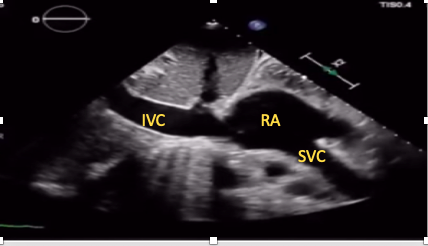

SC Bicaval View

This view allows simultaneous visualization of the superior and IVC as they join the right atrium (Figure 13). It can be particularly useful for guidance of extracorporeal membrane oxygenation cannula and central venous cannula position confirmation.15,28,29 Tilting the transducer slightly laterally while in the IVC view brings the superior vena cava into view in most patients.

Figure 13. SC bicaval view.

IVC= inferior vena cava, SVC= superior vena cava, RA= right atrium